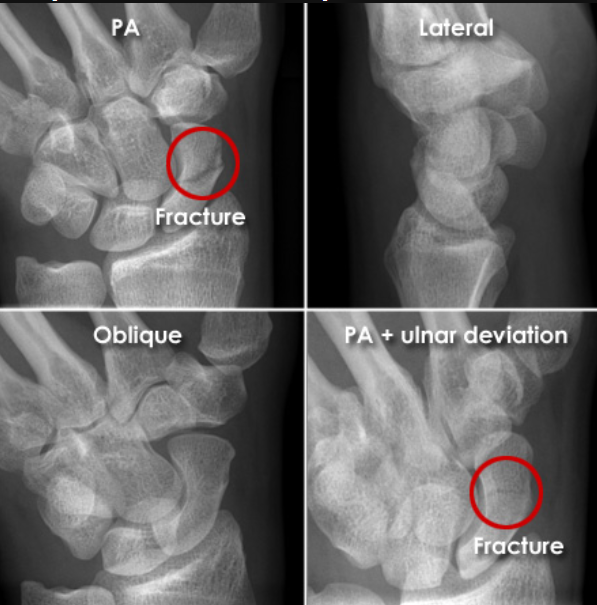

- 먼저 방사선 손목 사진을 찍어서 확인합니다. 그러나, 처음 방사선사진에서 나타나지 않더라도 골절이 의심되면 2-3주 후에 다시 찍어 재확인하여야 합니다. 필요한 경우에는 뼈스캔(bone scan), CT, MRI 등의 특수 검사를 하여 확인해야 합니다.

- 아래 엑스레이처럼 잘 관찰해야 보입니다.

- 특정 엑스레이 각도에서만 겨우 보이는 경우도 있습니다.